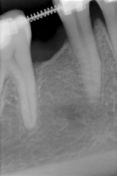

Impianto. Impianto Tixos 3,3 di diametro e 8 mm di lunghezza. Non è stato possibile inserire un impianto piu largo a causa del posizionamento distale dell'impianto e non centrale per la presenza del forame mentoniero. Questo è stato appena sfiorato come potete notare dalla rx di controllo. Un impianto messo più centrale comportava lo schiacciamento del forame. Nessuna sintomatologia parestesica riferita dalla paziente. Il caso è in attesa di protesizazione nei prossimi 4 mesi.